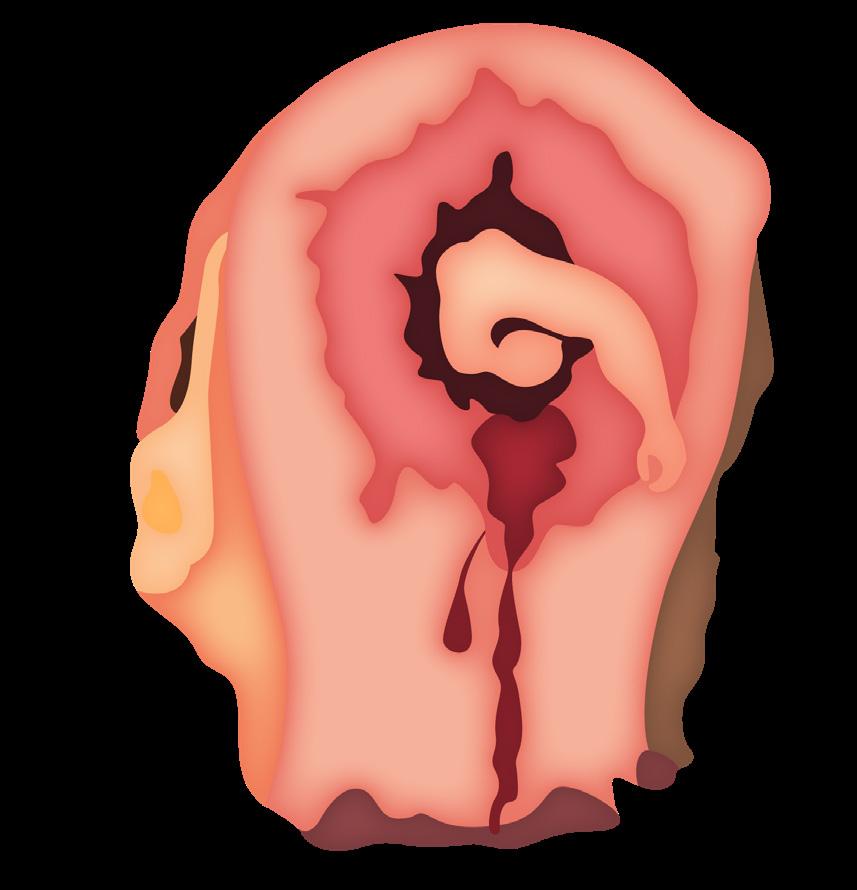

Certeza: La ecografía transvaginal es la prueba confirmatoria de embarazo. A las 4.5 semanas, se observa saco gestacional; a las 5 semanas, se encuentra embrión, y a las 6 semanas es posible auscultar los latidos cardiacos fetales con el doppler . También se considera la percepción de movimientos fetales por parte del médico.

Figura 11. Ecografía de I trimestre Examen de certeza para confirmar un embarazo eutópico y viable